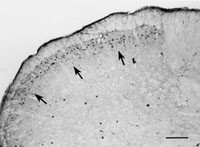

Med hjälp av immunhistokemiska tekniker har vi i studier på honråttor påvisat östrogenreceptorer i de ytliga lagren av ryggmärgens bakhorn, dvs i de områden där de perifera smärtspecifika nervtrådarna slutar och där den första omkopplingen av smärtsignalerna sker (8) (fig 1). Detta fynd har senare konfirmerats av andra forskargrupper (9, 10).